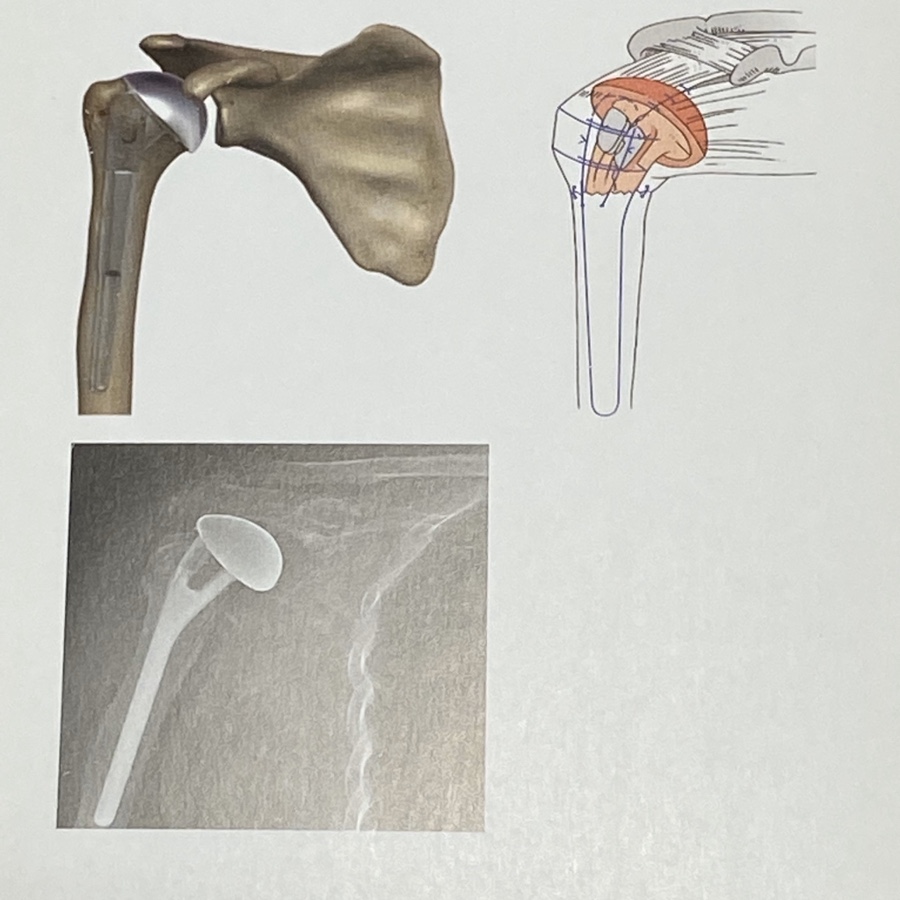

1.인공관절 반치환술

견갑골 관절와 손상이 없는 관절염 및

근위 상완골 복잡골절시 시행합니다

2. 인공관절 전치환술

상완골 두 빛 견갑골 관절와의 손상이 동반되는

관절염(퇴행성.류마티스.외상성),골괴사증 등에서

고려할 수 있습니다

3.역행성 인공관절 치환술

회전근 개 관절병증, 골유합이 힘든 고령의 근위

상완골 복잡골절.인공관절 재치환술시 시행합니다.

일반적 관절 치환술과는 달리 관절와 부분이 볼, 그리고

상완골 부분이 소켓 형태로 된 인공관절로서

회전근개가 없는 등의 특수한 경우에 사용 됩니다